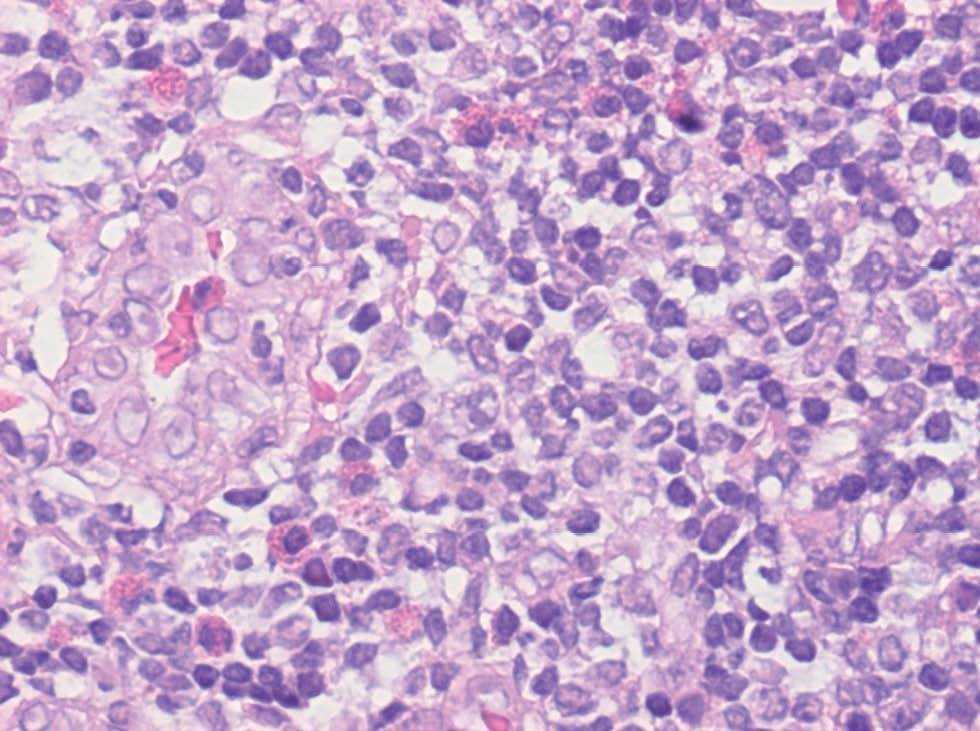

Fig. 2.--Aspecto histológico inflamatorio del nódulo.

En el estudio histopatológico se observó en dermis media-profunda e hipodermis una proliferación nodular e intersticial de vasos sanguíneos de tamaño y morfología uniforme acompañados de un intenso infiltrado inflamatorio de linfocitos que parecían constituir folículos linfoides y abundantes eosinófilos (fig. 2). Las células endoteliales eran prominentes, epitelioides, tenían un citoplasma eosinófilo y en algunos vasos se disponían en forma de empedrado o guijarros (fig. 3). Los estudios inmunohistoquímicos resaltaron que las áreas que parecían folículos linfoides expresaban CD 20 en el centro y CD 43 en la periferia. El estudio genotípico no demostró clonalidad del gen de cadenas pesadas de las inmunoglobulinas. La tinción con CD 31 fue positiva y con factor VIII débilmente positivo, lo cual apoyaba la naturaleza vascular de la lesión. Se realizó una eco-Doppler que descartó un shunt arterio-venoso subyacente.

Histológicamente se caracteriza por la existencia en dermis e hipodermis de nódulos que presentan dos componentes: vascular e inflamatorio. El componente vascular se caracteriza por abundantes luces vasculares de morfología irregular cuyas células endoteliales protuyen hacia la luz presentando el típico aspecto en tachuela; a veces adoptan una morfología epitelioide o histiocitoide. En ocasiones es muy típico que las células endoteliales se agrupen y presenten un aspecto en empedrado o en guijarros, forman nidos sólidos sin luces vasculares. El componente inflamatorio que aparece alrededor de los vasos está formado por linfocitos, eosinófilos y mastocitos. En un 10 % de los casos se observan folículos linfoides y centros germinales. Las tinciones de inmunohistoquímica para células endoteliales, incluyendo factor VIII, CD 31 y Ulex europaeus, son positivas y permiten confirmar el diagnóstico 2.